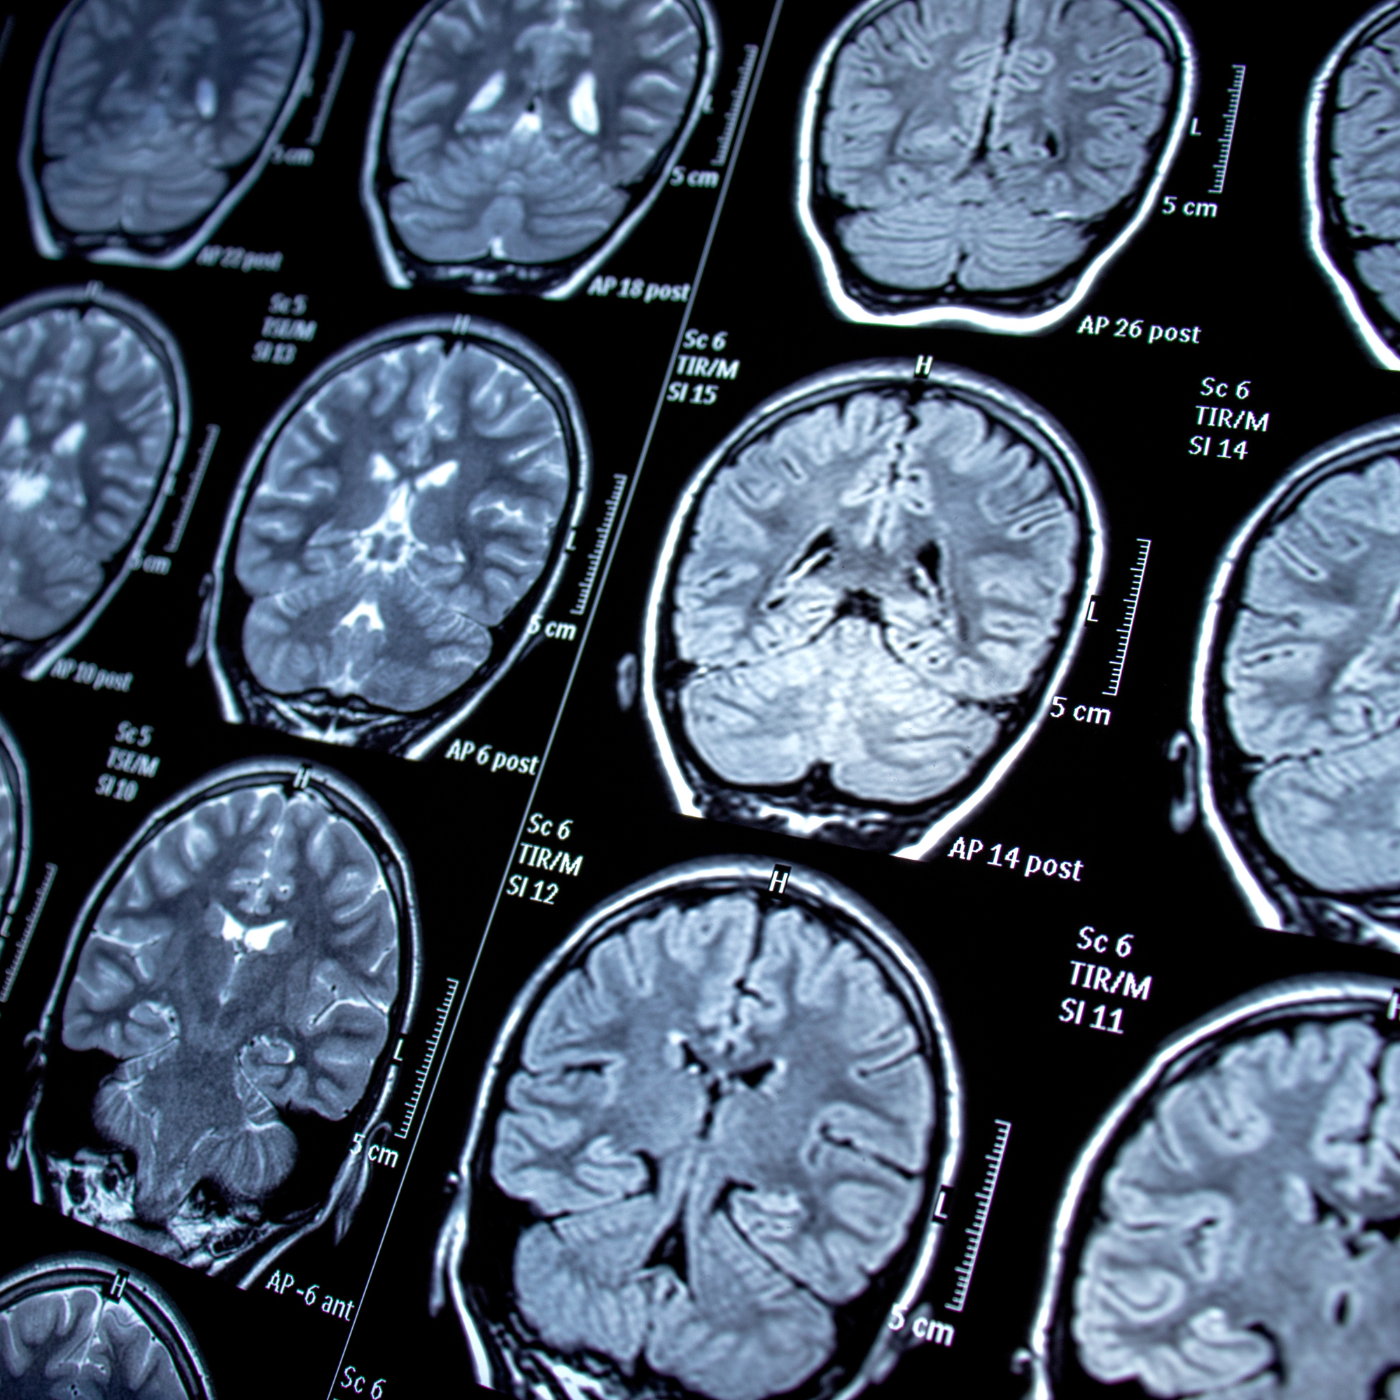

Magnetic Resonance Imaging Or (MRI)

Magnetic Resonance Imaging or (MRI) Scans are also very important as they are related to testing of the nerve system and internal tissues and for a look on the internal functioning of the body hence in any case of medical emergency a doctor can prescribe a MRI Scan and thus, we created our 24/7 service for MRI scans so you don’t have to take a chance with the health of your loved ones no matter what time it is.